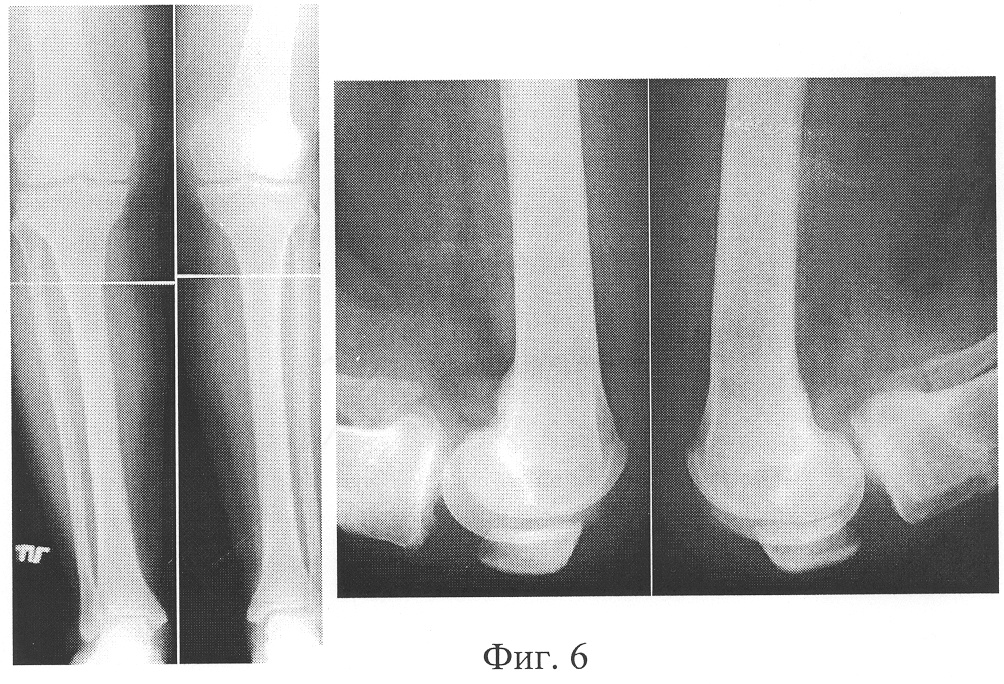

Фиг.3 – рентгенограммы правой нижней конечности пациентки до лечения;

На рентгенограммах коленных суставов: варусное отклонение голеней 10° во фронтальной плоскости. Суставная щель в медиальном отделе сужена, а в латеральном расширена (Фиг.3). На рентгеноконтрастных артрограммах коленных суставов в подколенных областях визуализируются кисты Бейкера (Фиг.4).